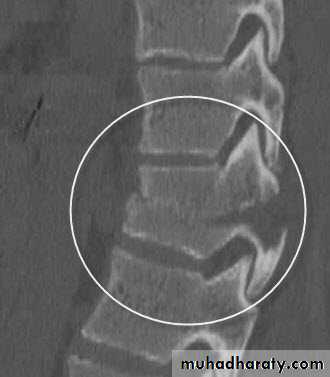

FLEXION-DISTRACTION = SEAT-BELT-TYPE = CHANCE # :

• Posterior &middle columns failure. (hyperflexion then tension forces)• Anterior column functions like a hinge.